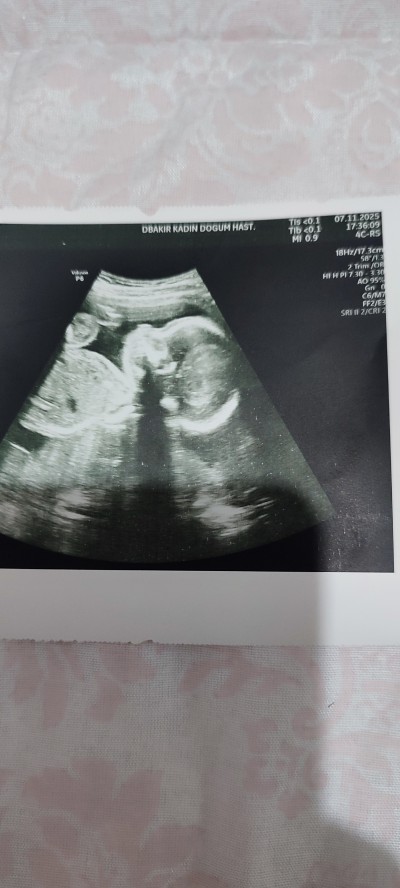

kizlar oğlumun gelişimi yine iki hafta öndeydi ama maalesef kilosunu sormayı unuttum burda yazıyor mu kilosu anlayan cevap verebilir mi rica etsem şimdiden teşekkürler ❤️

Gebelik haftası 21+3

Canm EFW  yazsiin yanında kilosu yazar bu yazı var mı bı bak istersen bende de aynı çünkü ultrasona resmi ona göre bakıp söyledim sana yada AC.BPD FLyazar bı bak ister bu ikisinden birinde kilosu yazar

Kilosunun yazdığı ultrason kağıdı daha uzun oluyor cnm bi bolum sadece kilo boy ve haftasi fln yazar

Maaşallah cnm .bebek kilosu normalde sol tarafta yazılıyor diye biliyorum.onu da çekmemişsin sanırım

Yok canım sol taraf boş bişey yazmıyor orda